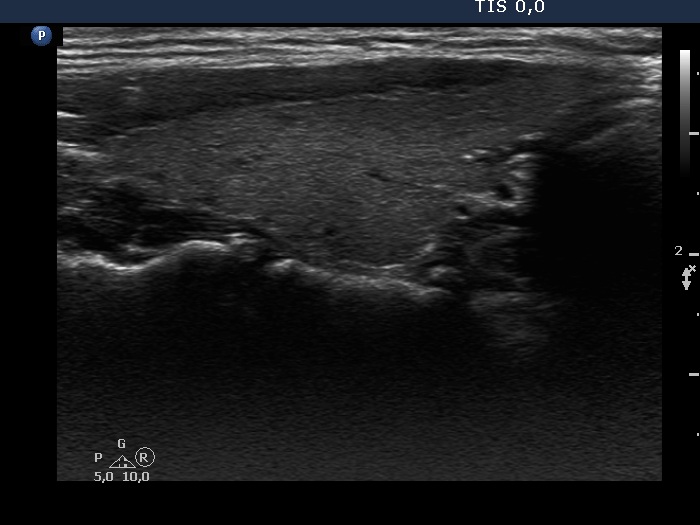

Consecutive patients with the final diagnosis of Hashimoto's thyroiditis - case 54 (767) (ultrasonographic picture 2)

Right lobe, longitudinal view. There are tiny hypoechogenic areas.